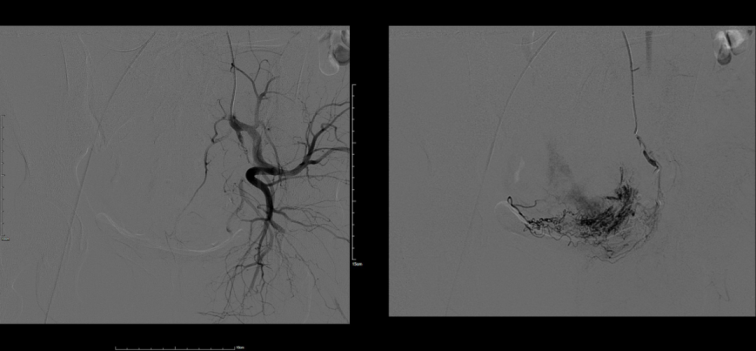

我院科教院長(zhǎng)、婦產(chǎn)科專家盧北燕、婦科主任劉小立帶領(lǐng)婦科團(tuán)隊(duì)認(rèn)真分析患者病情,入院診斷為:剖宮產(chǎn)術(shù)后子宮瘢痕妊娠。為了保留患者的生育功能,確保患者生命安全,我院婦科在患者入院第一天行子宮動(dòng)脈栓塞介入手術(shù),隔日于全麻下行宮腔鏡檢查術(shù)+宮腔鏡剖宮產(chǎn)瘢痕妊娠病灶切除術(shù)。術(shù)后病理送檢組織為妊娠絨毛、滋養(yǎng)細(xì)胞、蛻膜及凝血組織?;颊咝g(shù)后恢復(fù)良好,三天出院。

子宮動(dòng)脈栓塞與清宮術(shù)或?qū)m腔鏡手術(shù)結(jié)合,是目前臨床上較為常用的治療方式。經(jīng)股動(dòng)脈插管向子宮動(dòng)脈注入栓塞劑能迅速有效止血;栓塞后在B超或?qū)m腔鏡監(jiān)視下清除胚囊絨毛,使術(shù)中大出血的風(fēng)險(xiǎn)大大降低。目前,我院婦科已經(jīng)成功開(kāi)展多例此類介入手術(shù),深得廣大女性患者的認(rèn)可。未來(lái),佳木斯大學(xué)宏大醫(yī)院全體醫(yī)護(hù)人員將一如既往地為三江百姓健康保駕護(hù)航。